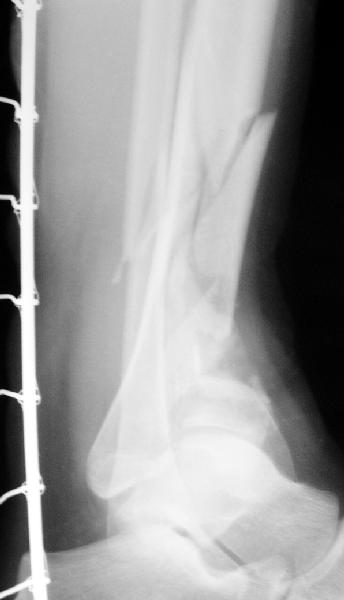

Пластинка красивая. Чуть только спереди назад идет, не сосем по оси большеберцовой кости. А там не маловато фиксаторов собственно в дистальном суставном конце кости? А вправляли его как? Как будто или осталось запрокидывание кзади или недонизведен передний край. Но с учетом исходного тяжелейшего повреждения - все равно здорово.

А была ли необходимость менять аппарат на такую пластину? Выигрываем в возможности более ранней разработки голеностопного сустава?